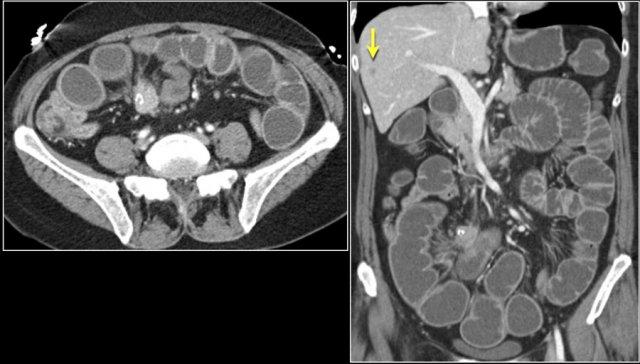

Đây là bệnh nhân u hắc tố di căn.

Hình bên trái cho thấy lồng ruột hồi-hồi do tổn thương di căn.

Hình bên phải cho thấy lồng ruột trên mặt phẳng coronal, cùng với một hạch bạch huyết mạc treo phì đại (mũi tên vàng) và di căn gan lan rộng.

Bệnh nhân này có nhiều khối trong lòng ruột non (mũi tên vàng), được xác định là di căn từ u nguyên phát không rõ nguồn gốc.

Cũng lưu ý hình ảnh lồng ruột (mũi tên đỏ) và tổn thương di căn mô mềm ở cơ mông trái (mũi tên xanh lam).